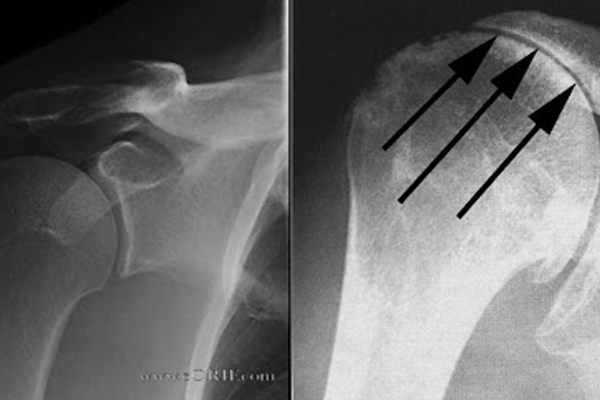

ROTATOR CUFF TEARS